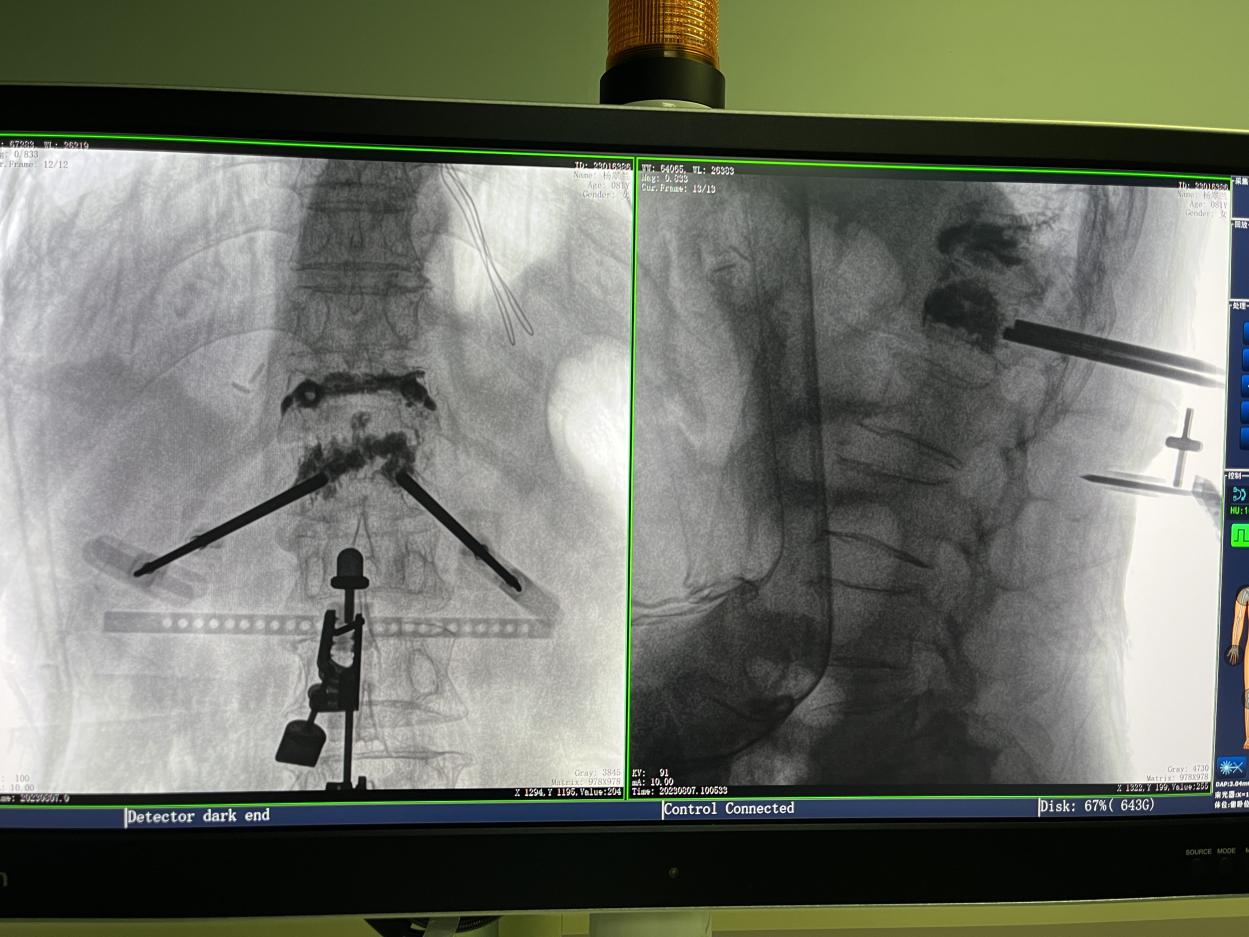

1.三維術(shù)中圖像

PL300B搭配普愛醫(yī)療自主研發(fā)生產(chǎn)的平板三維C形臂使用,通過三維立體術(shù)中圖像,手術(shù)醫(yī)生可從各個方位觀察合適的手術(shù)入路,并進(jìn)行關(guān)鍵數(shù)據(jù)測量,從而最大限度地避開危險區(qū)。

骨科機(jī)器人手術(shù)-術(shù)中影像